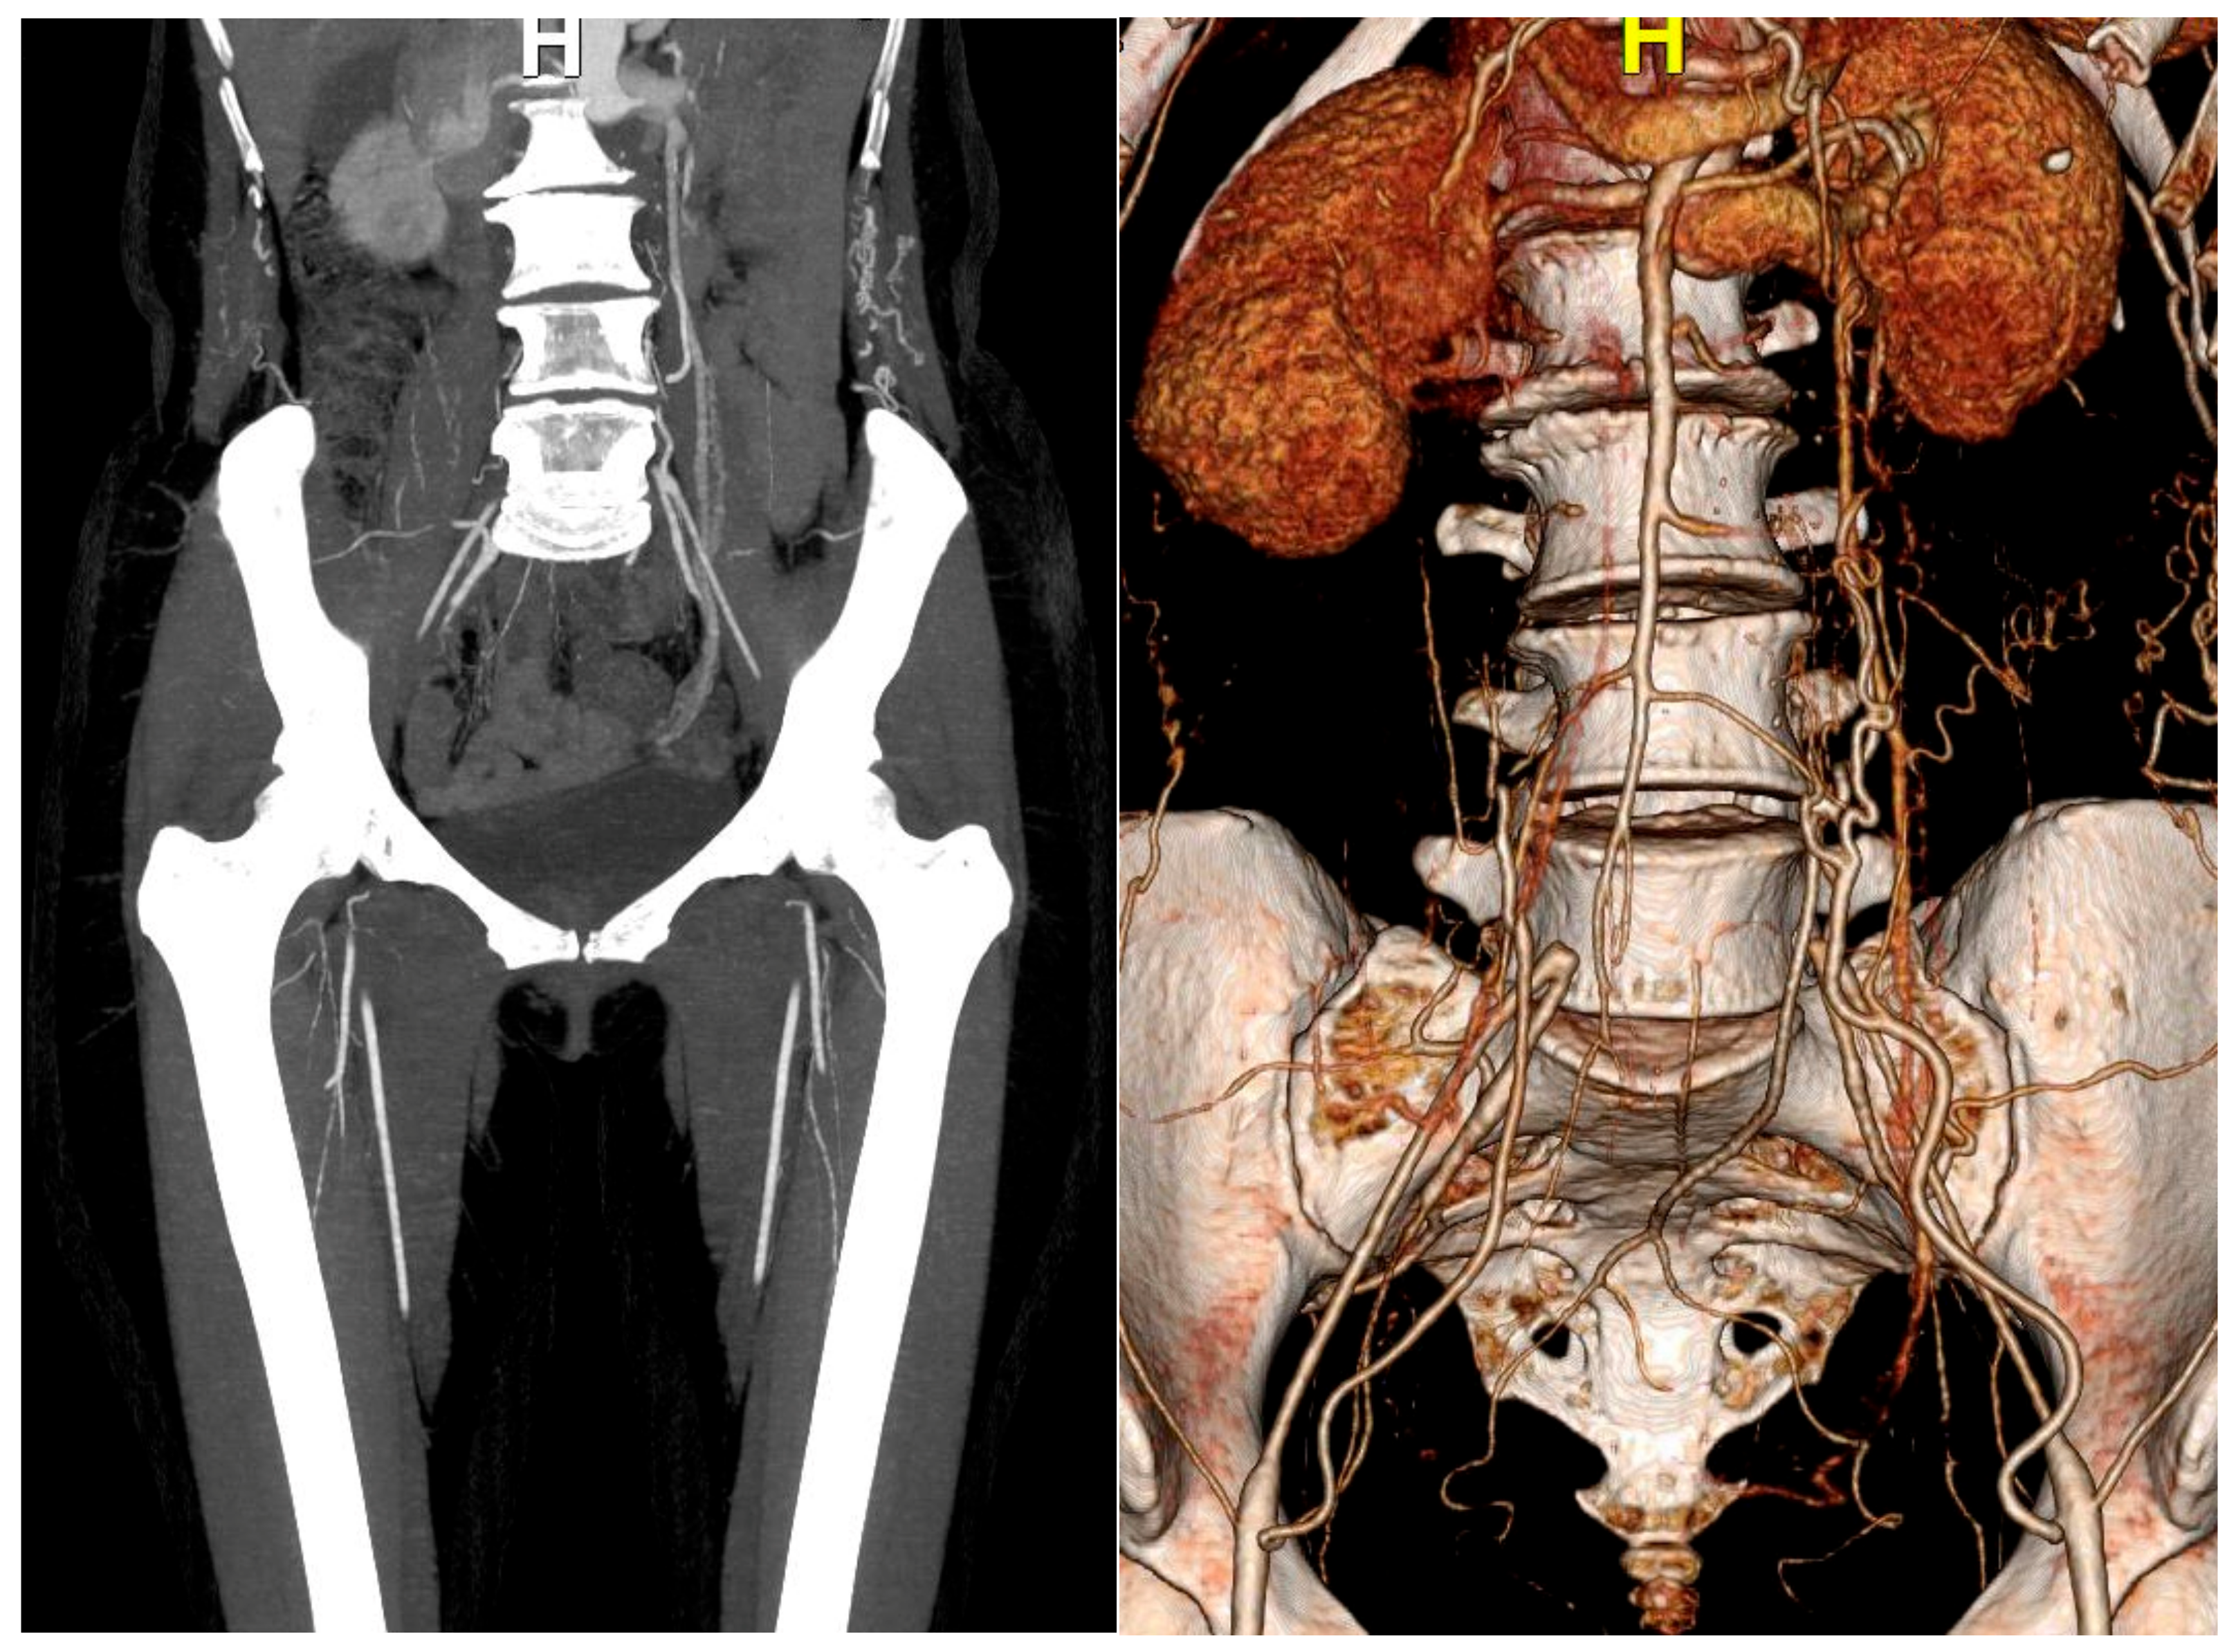

2. Case Report